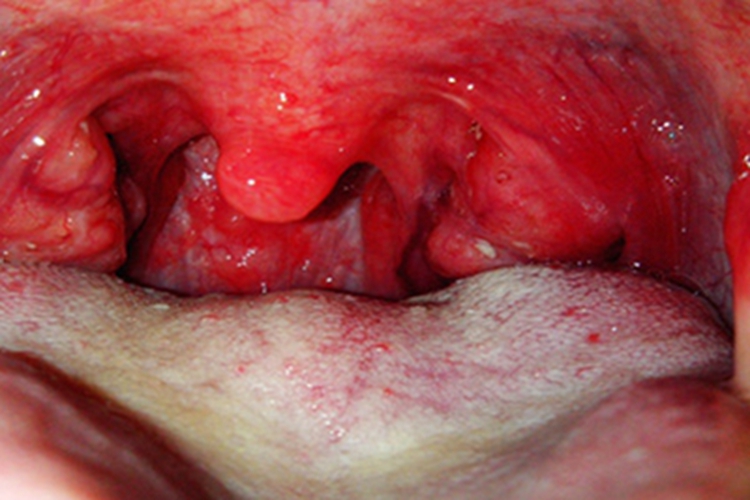

急性化脓性扁桃体炎导致的损害可表现为扁桃体充血、肿胀、发红,轻重不定,有时表面出现点状渗出物,黄白色,可伴有咽痛、吞咽困难等不适症状。